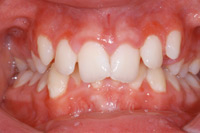

Eine erste Zahnfehlstellung kann sich schon im

Kindesalter durch falsche Angewohnheiten ergeben

(Engl. "bad habits"). Diese falschen Angewohnheiten

sind Daumenlutschen, Lippensaugen bzw. Lippenbeissen

[4] oder dauerndes Nuggeln an der Trinkflasche oder am

Schnuller (alemannisch: Nuggi) [5]. Die vorderen

Schneidezähne werden dann jeweils nach oben gehoben,

der Kiefer wächst falsch, und das Gebiss weist dann

vorne ein grosses "Loch" auf [8].

Durch zu

viel Daumenlutschen oder Sauger

(Flaschensauger oder Nuggi) ergibt sich

die Zahnfehlstellung des "offenen Biss"

bei den bleibenden Zähnen. [5]